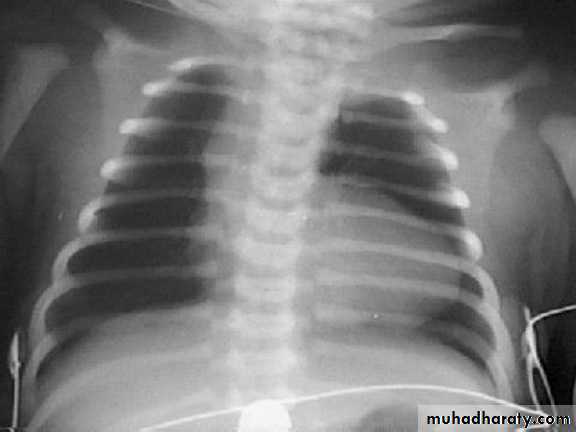

Coeur en sabot (boot-shaped heart) secondary to uplifting of the cardiac apex from RVH and the absence of a normal main pulmonary artery segment

Normal heart size due to the lack of pulmonary blood flow and congestive heart failure

Decreased pulmonary vascularity

Right atrial enlargement

Right-sided aortic arch (20-25% of patients) with indentation of leftward-positioned tracheobronchial shadowEchocardiography